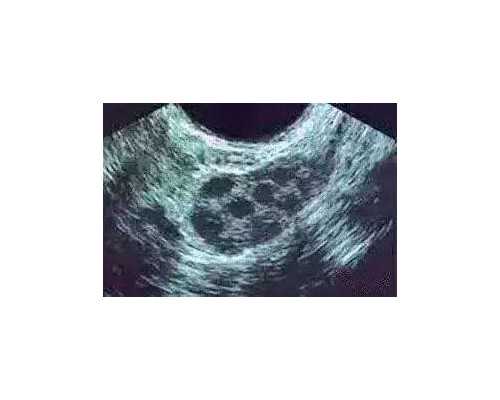

试管囊胚5天可以进行基因检测,但需要等待3-5天才能得到结果。通过PGS和PGD筛查,可以帮助夫妇选择健康的囊胚并避免某些遗传疾病。当然,试管囊胚基因检测也存在一些缺点,需要夫妇在选择时进行权衡。